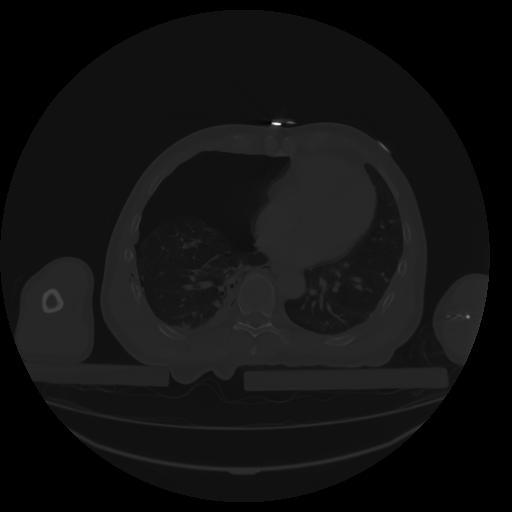

27 CUERPO,CE,Axial,3.0,CUERPO,,